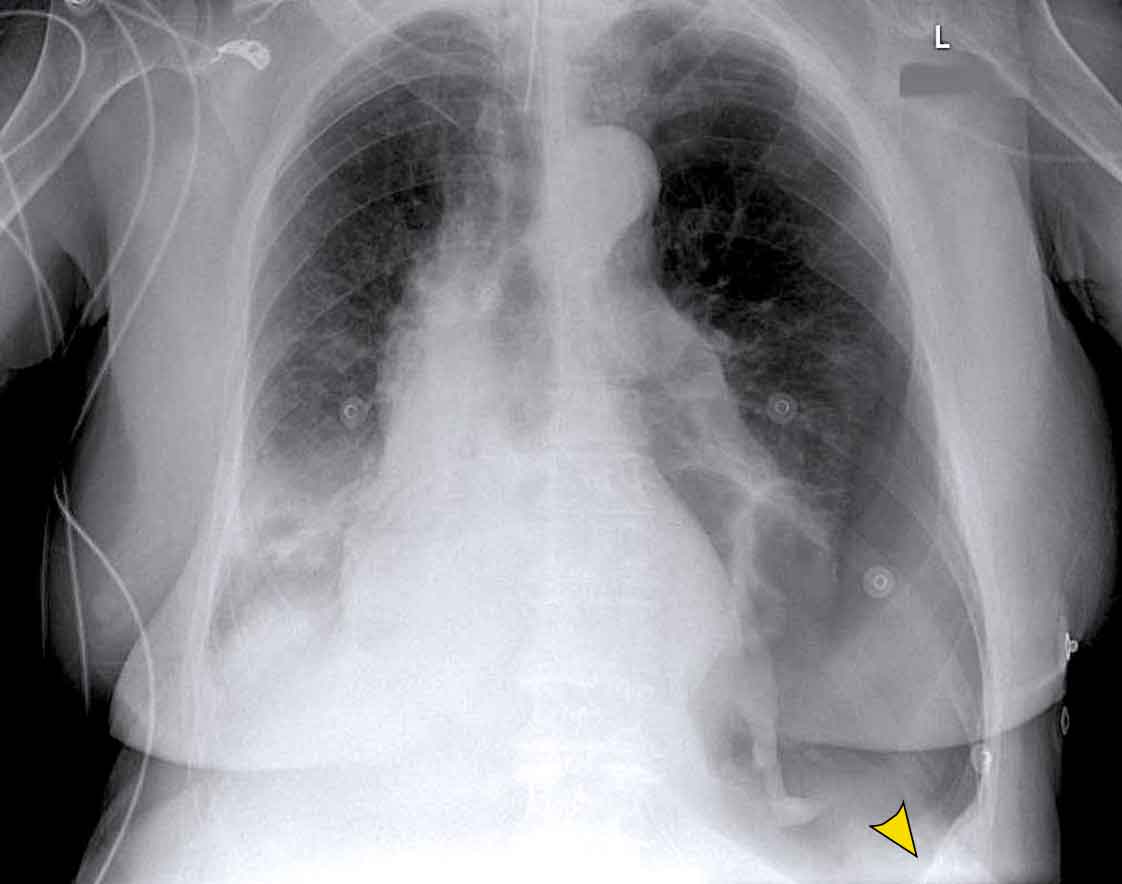

Displacement of the Azygoesophageal Line (1) – Hiatal hernia

A hiatal hernia (arrowheads) is the most common cause of displacement of the azygoesophageal line as seen on the PA-view.

Notice the air within the hernia on the lateral view (black arrow).